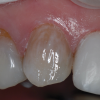

(4.) Pretreatment and posttreatment close-up photographs of maxillary central incisors treated with internal bleaching and direct composite veneers.

Figure 4

(5.) Pretreatment and posttreatment close-up photographs of maxillary central incisors treated with internal bleaching and direct composite veneers.

Figure 5

Sometimes, internal bleaching may be insufficient to raise the value of the tooth to the extent that the patient desires, or the patient's desired esthetic outcome may not be completely achieved with internal bleaching. One viable, conservative treatment modality to help manage a discolored tooth is to utilize a composite veneer (Figure 4 and Figure 5). When compared with indirect veneers, direct composite veneers are oftentimes more affordable as well as more readily repairable and typically less invasive.9 Composite veneers may also be beneficial to both the clinician and patient because they do not have to be provisionalized, do not involve a laboratory fee, and do not require impressions. In some cases, local anesthesia may even be avoided. This treatment modality also allows the patient to provide the dentist with immediate feedback about the color, optical properties, and design of the veneer with no need to then send it back to the laboratory to be recreated. The downsides of composite veneers include that they are more technique sensitive to place and that composite is more susceptible to discoloration and loss of surface gloss.10 If this treatment modality is to be used, the clinician must consider the patient's opposing dentition, caries risk, and occlusion, among other factors.